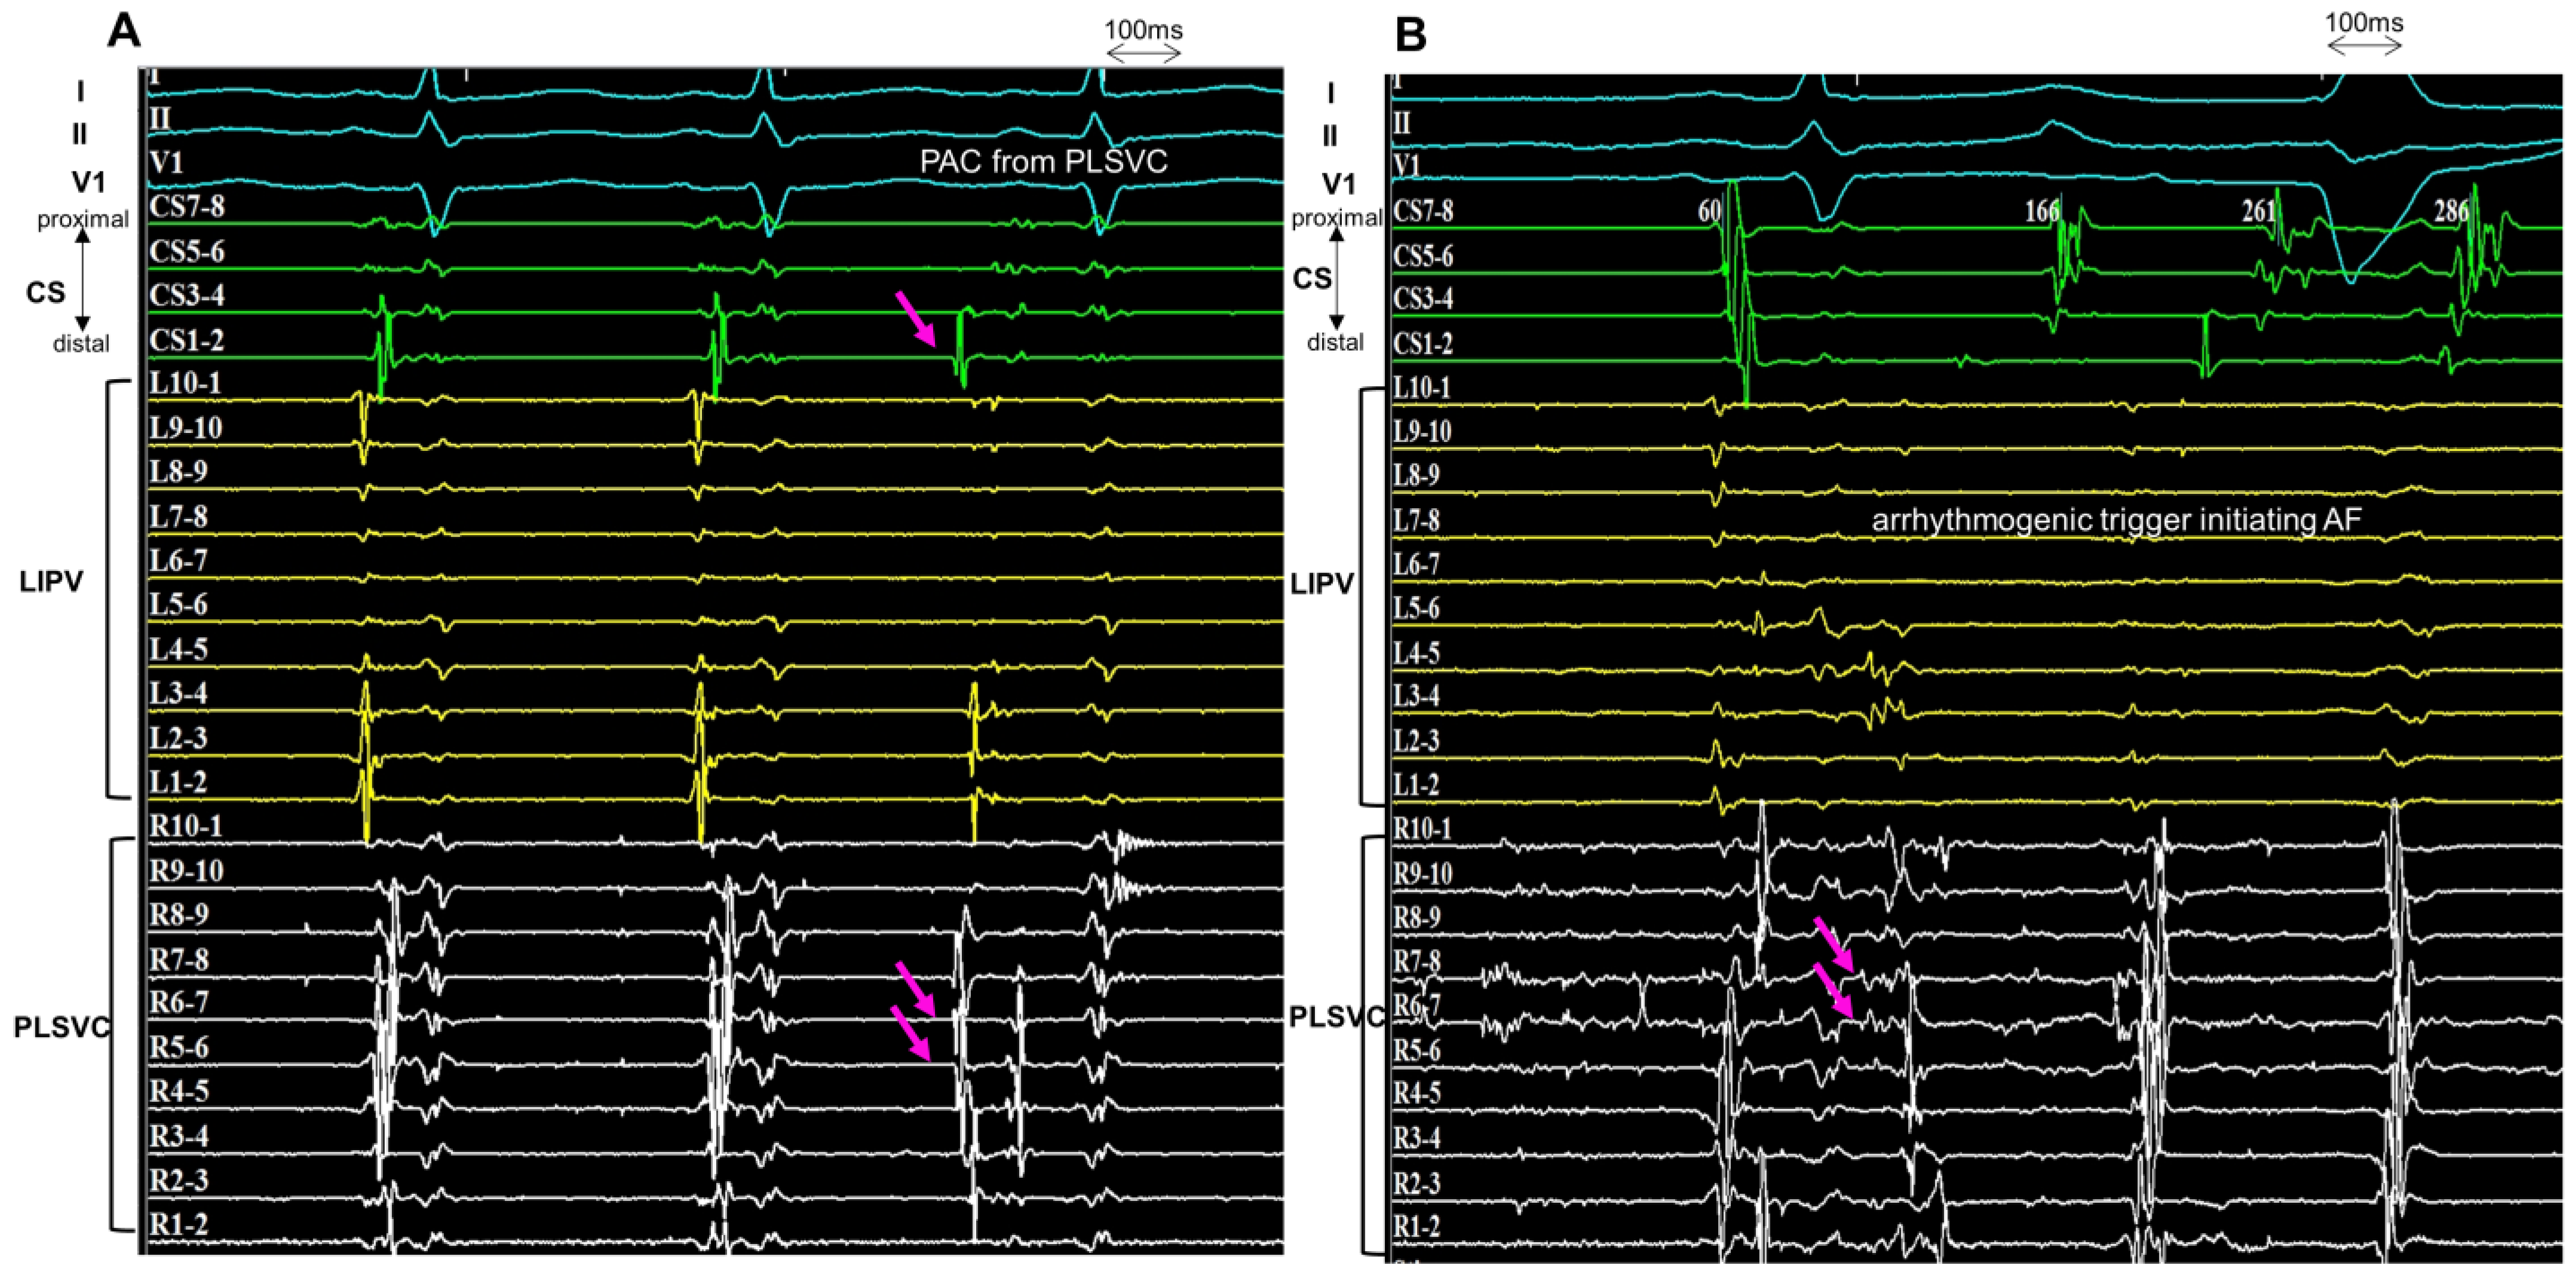

3.2. Provocation of Arrhythmogenic Triggers from Persistent Left Vena Cava

3.3. Localization of Triggers and Electrical Isolation of Persistent Left Superior Vena Cava